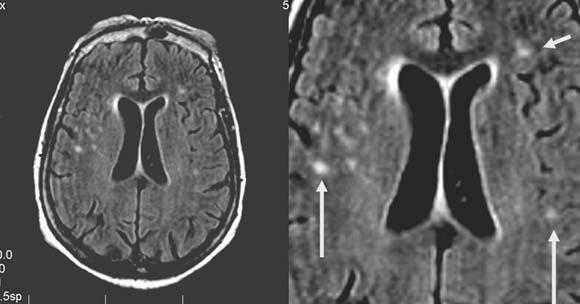

Одно из преимуществ МРТ в оценке последствий инсульта - возможность визуализировать нисходящую Валлеровскую дегенерацию аксонов в стволе мозга и кортико-спинальном тракте на стороне поражения.

Валлеровская дегенерация вследствие инсульта в бассейне средней мозговой артерии в левом полушарии большого мозга. Р1_А1К-изображения (а, b) и Т2-ВИ в аксиальной плоскости (с). В зоне, кровоснабжаемой левой средней мозговой артерией, визуализируется кистозный дефект с глиозом (а). Определяется повышенная интенсивность сигнала от пирамидного пути в левой ножке мозга (b) и в продолговатом мозге слева (с).